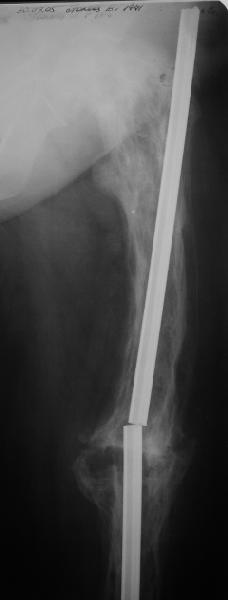

Еще один пример. Пациентка с юга России, прислала рентгенограммы через

год. На сегодня прошло 2 г. 8 мес. после операции. Несмотря на не очень

убедительный процесс сращения, пациентка ходит. Учитывая остеопороз при

Педжете, решили, что динамизировать вообще не нужно.